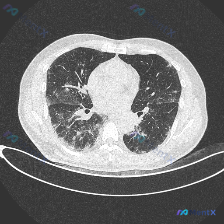

分享一个胸部CT病例,先整理资料再分析: 影像基本信息 - 图像类型:胸部CT肺窗横断面 - 解剖层面:主动脉弓下方至气管分叉上方(主动脉弓及主肺动脉窗层面) - 图像质量:清晰度尚可,无明显呼吸运动伪影 核心影像学表现 肺实质异常 1. 弥漫性间质性改变:双肺可见弥漫性磨玻璃密度影,伴细小网格状影...